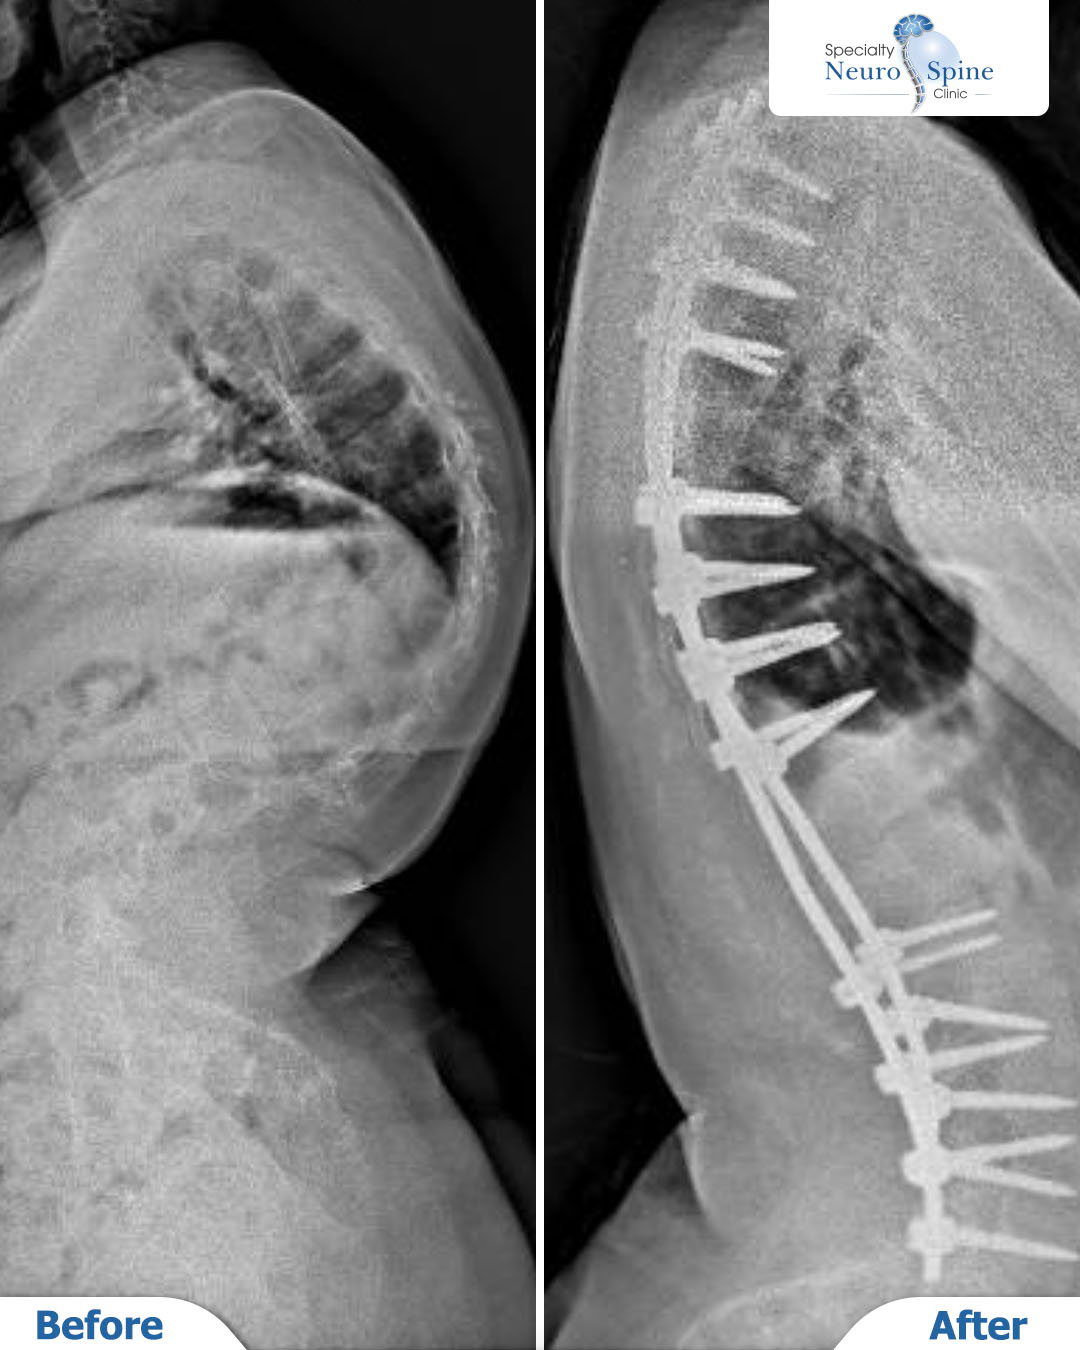

مريضتنا العزيزة زينب، 16 عامًا من البحرين، عانت من ورم في العمود الفقري وخضعت لعدة عمليات سابقة في ألمانيا لإزالته.

لكنها لم تُنصح حينها بإجراء عملية تصحيح الانحراف نظرًا لخطورتها.

بعد مراجعة حالتها بدقة من قبل الدكتور فراس الحُسبان، طمأن العائلة وأكد إمكانية إجراء العملية بأمان بفضل التقنيات الحديثة المتوفرة لديه.

اليوم، وبعد نجاح العملية، نشارككم هذه اللحظة التي تعكس استقامة العمود الفقري واستقرار الحالة.